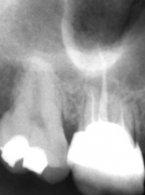

Podczas leczenia endodontycznego zęba 37 (dolny lewy drugi ząb trzonowy żuchwy) u 48-letniego mężczyzny pacjent zasygnalizował ból. Doszło do tego w trakcie wypełniania kanału korzeniowego pastą jodoformową. Ból obejmował lewą stronę twarzy, promieniował do pozostałych zębów lewej strony żuchwy i do okolicy lewego kąta ust. Na zdjęciu zębowym wykonanym bezpośrednio po pojawieniu się bólu zdiagnozowano zacienienie rzutujące się w przebiegu kanału żuchwy. Jakie powinno być postępowanie po przepchnięciu materiału do kanału żuchwy i jak można uniknąć takiego powikłania?